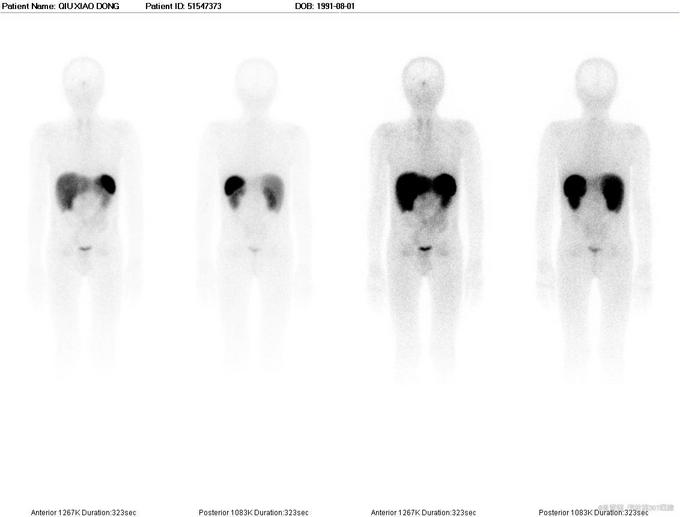

查体:神志清楚,不能独立行走,消瘦体型,胸廓、腰骶部、颈椎等多处骨骼有明显压痛。心肺腹未见明显阳性体征。 辅助检查:PTH:86.61(15-65pg/ml);25-D3:5.8(20-32);ALP:264.8(0-130u/l);血P:0.34(0.89-1.6mmol/l);血Ca:2.2(2.09-2.54mmol/l);骨密度:严重骨质疏松;X线:可见病理性骨折。奥曲肽显像:垂体瘤不除外。颈部CT:左侧甲状旁腺不除外结节样改变。